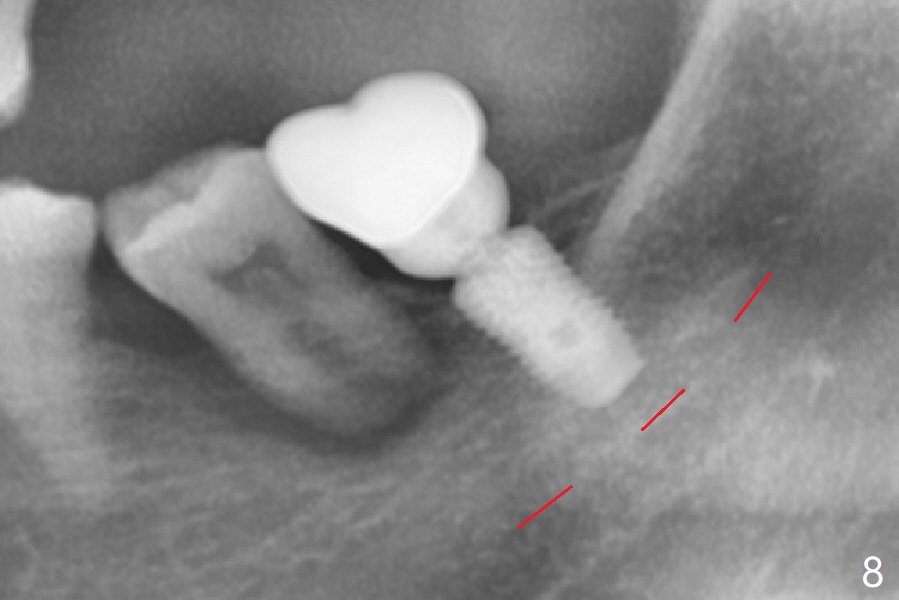

After extraction, curettage and Clindamycine gauzes in the sockets of the tooth #18 for 3 times, a 2 mm pilot drill makes initial osteotomy in the socket from 8 to 14 mm (Fig.1 (gingival level)). It appears that the osteotomy should move distal (Fig.1: red line, Fig.2 (17 mm)). After 5.9x10 mm drill, a 5.9 mm tap is placed (Fig.3). There is 4 mm clearance. Following 6.4x10 mm drill for 2 mm deeper, a 6.4x10 mm implant is placed with 60 Ncm. The implant plateau is level with the lingual crest, while the mesiobuccodistal bone is low. Autogenous bone mixed with Osteogen is placed in the defect area, followed by insertion of a 6.8x4(4) mm abutment (Fig.5). Collagen dressing is placed on the top of the graft. An immediate provisional is fabricated to close the remaining socket. Impression is taken 7 months postop (Fig.6). There seems to be no bone loss 23 months post cementation without opposing teeth (Fig.7) in spite of severe periodontitis at #19 (Fig.8 (25 months post cementation)). More surprising is the asymptomatic lingual (L) plate perforation, revealed by CT (Fig.9 arrowheads).